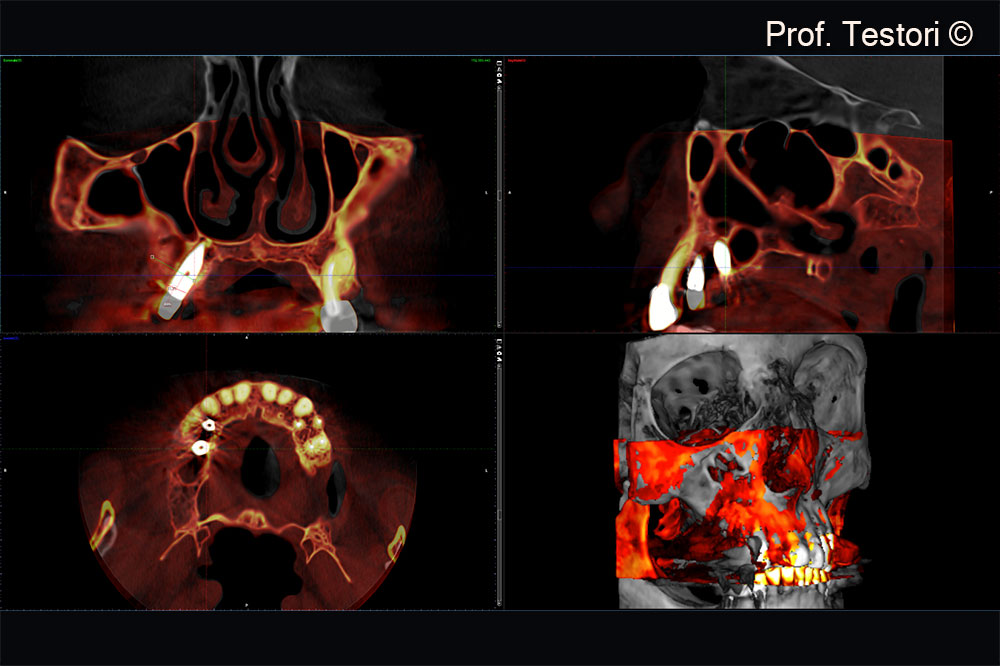

Cone-beam computerized tomography exam after 4 months of healing.